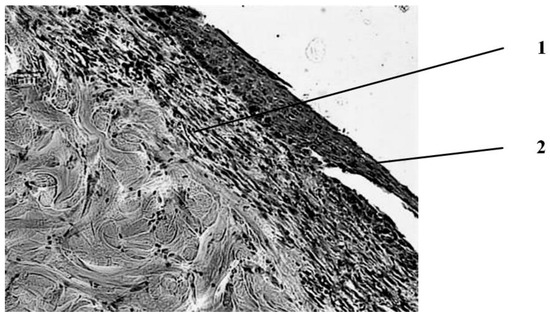

Seven days after the injury, the animals in the wounds of the control group (treatment with Levomecol) showed a picture of inflammation with initial signs of healing (Figure 2).

The wound is covered with a scab, which consists of necrotized tissues (epidermis, dermis), and in the center of the wound, where the burn was deepest, its own muscle is included in its skin. On the periphery, closer to the edges of the wound, approximately in the middle of the thickness of the dermis, a pronounced leukocyte demarcation shaft is found, which divides the dermis into three parts—upper, necrotized, and lower—with manifestations of regeneration in the form of proliferation of epithelial cells in the course of pre-existing hair follicles and initial manifestations of marginal epithelialization of the wound, foci of fibroblast proliferation in the dermis with the appearance of newly formed collagen fibers and thin-walled blood vessels, and in muscle tissue against the background of dystrophically altered, and even necrotized muscle fibers with the phenomena of sarcoplasm decay are sometimes found as manifestations of regeneration in the form of muscle kidneys. Proliferation of myocyte nuclei is noted along the periphery of a significant part of viable muscle fibers. In addition, fibroblasts proliferate between muscle fibers. In the loose connective tissue under the skin’s own muscle, there is a proliferation of connective tissue cells in these areas.

Figure 2. Morphological changes in the wound seven days after the application of the burn and subsequent treatment with Levomecol ointment. Initial manifestations of marginal epithelialization. 1—scab; 2—regenerating epidermis with signs of regeneration (beginning of marginal epithelization). Staining with hematoxylin and eosin. magn. ×50.